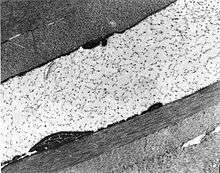

| The cornea is particularly opaque in the anterior stroma by slit-lamp biomicroscopy | |

Congenital stromal corneal dystrophy (CSCD), also called Witschel dystrophy, is an extremely rare, autosomal dominant form of corneal dystrophy.[1] Only 4 families have been reported to have the disease by 2009.[2] The main features of the disease are numerous opaque flaky or feathery areas of clouding in the stroma that multiply with age and eventually preclude visibility of the endothelium. Strabismus or primary open angle glaucoma was noted in some of the patients. Thickness of the cornea stays the same, Descemet's membrane and endothelium are relatively unaffected, but the fibrills of collagen that constitute stromal lamellae are reduced in diameter and lamellae themselves are packed significantly more tightly.